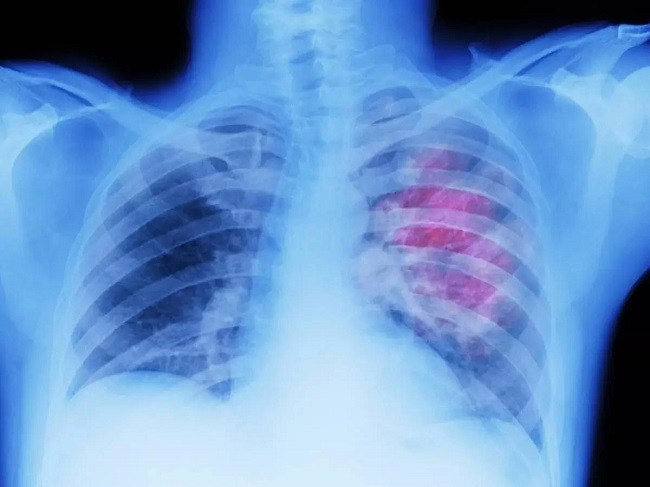

2 Lungs and lung cancer

Problems such as coughing, shortness of breath and sinus all decrease and disappear within 1 to 8 months of not smoking. Cilia again grow in your lung to cleanse and lower infection in your body. You find your ability for physical activity and walking increases and your lung function increases by 30%. Within 10 years off tobacco, the risk of fatal lung cancer becomes the same as non-smoker. Cancerous cells have all been replaced and cancer risk is significantly reduced.